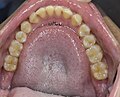

Here follows an example of human bite on a right forearm, with its evolution and a view of the teeth: